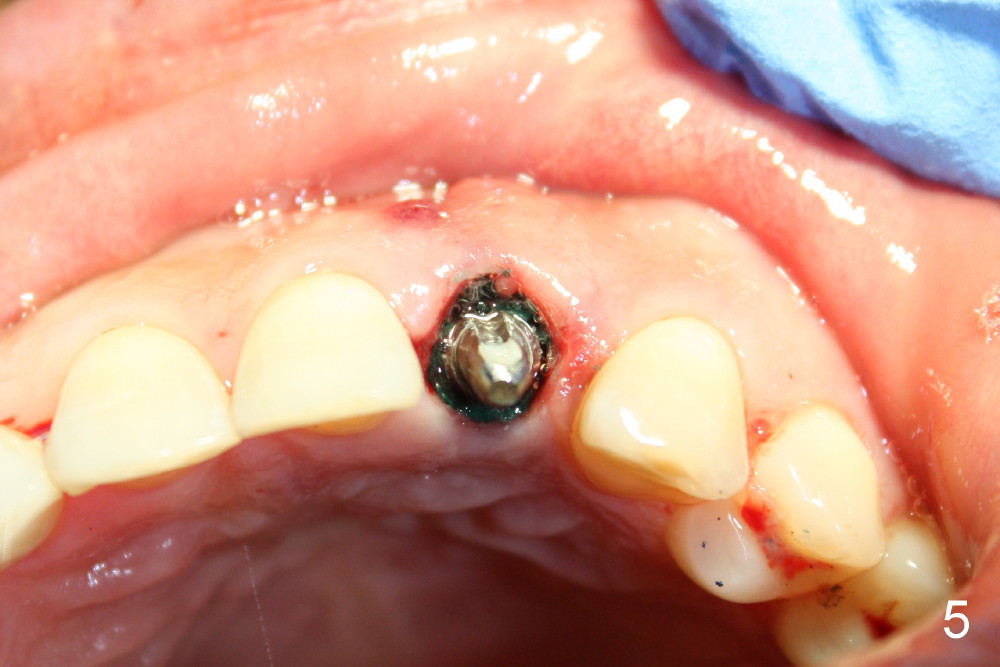

A 49-year-old lady has failed endo on the upper left lateral incisor (Fig.1,2). A gutta percha inserted to the buccal fistula (Fig.1 >) shows a mesial defect (Fig.2<). There is a large buccal apical defect, corresponding to the lesion shown in Fig.2 *, when the affected tooth is extracted. After thorough debridement and Clindamycin soaking, osteotomy is initiated in the palatal wall of the socket. Demineralized freeze dry cancellous bone graft is placed in the buccal defect. A 4x20 mm gingiva-level tapered implant is placed with insertion torque 50 Ncm (Fig.3). A 3x5 mm 20 ° offset abutment is inserted and cemented (Fig.4,5). A retentive groove is prepared on the abutment and the underlying implant; chamfer margin placed on the implant (Fig.4,5). A provisional is fabricated and cemented temporarily (Fig.6,7). Excess cement is removed, followed by removal of gingival retraction cord. There is no contact in centric and non-centric occlusion.